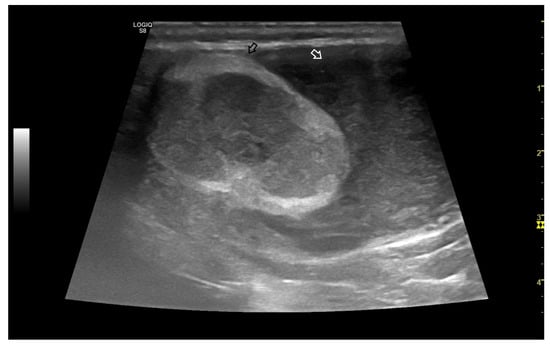

3.4.1. Intratesticular Diseases

3.4.2. Extratesticular Diseases

4. Colour Doppler and Power Doppler

4.4. Abnormal Findings